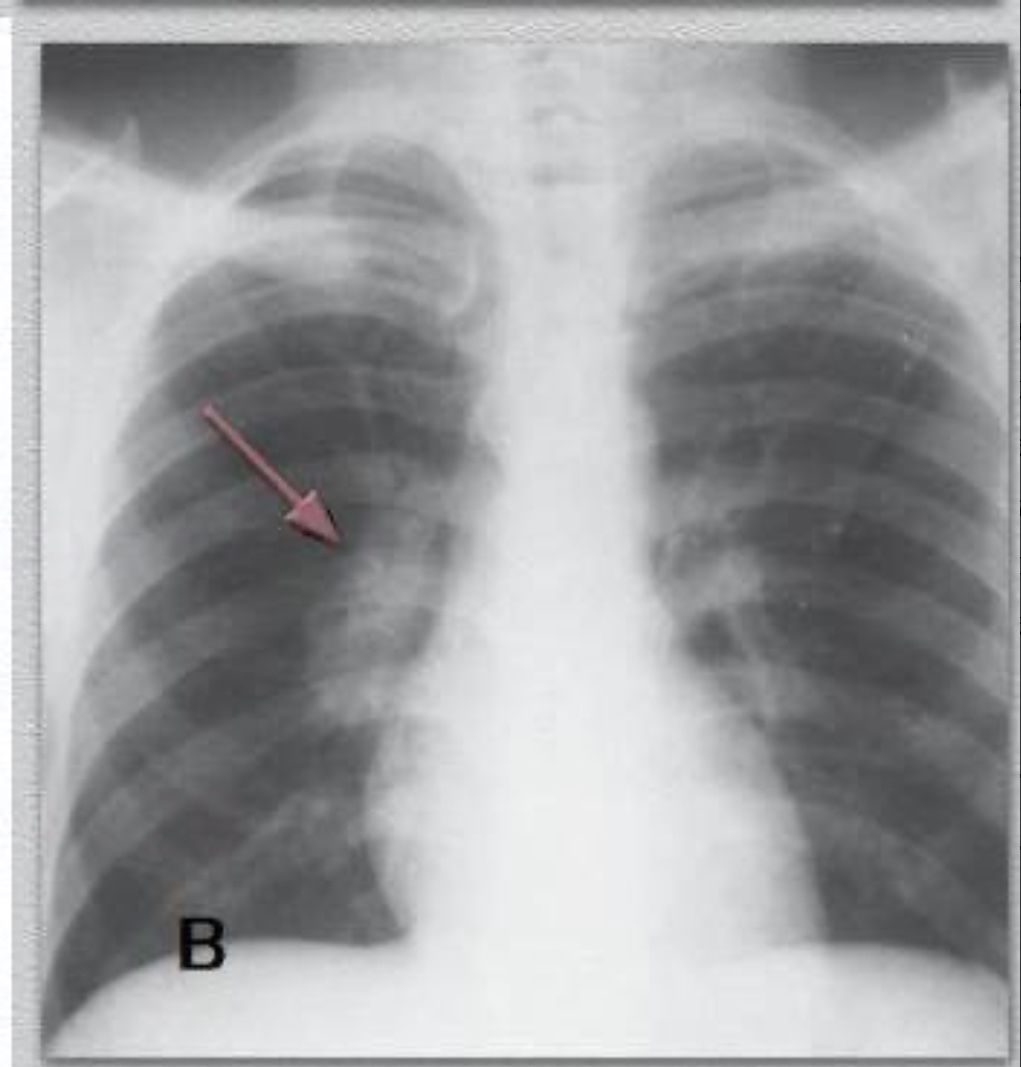

Como você interpreta esta imagem de um pct pediátrico com suspeita de TB?

Adenopatia hilar unilateral